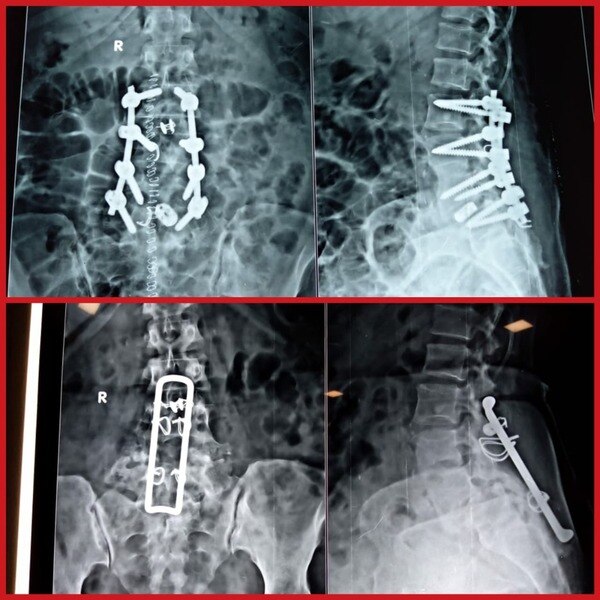

Dr. Rahul Chaudhari is a Reliable and Best Spine Surgeon, Spine Doctor, Spine Specialist in Bavdhan, Pashan, Sus, Bhugaon and Pune. Dr. Rahul Chaudhari is the USA trained Orthopaedic Spine Surgeon in Pune. He completed his MBBS/MS from KEM Hospital, Mumbai. He had received advanced spine/scoliosis surgery training in America for 3 years. His expertise involves treating cervical, thoracic, and lumbar spine disorders including degenerative spine conditions (slipped disc, sciatica, and spinal stenosis), fractures, tumors, and spinal deformities. He successfully treated many happy patients in his 17 years of journey as an Orthopedist.